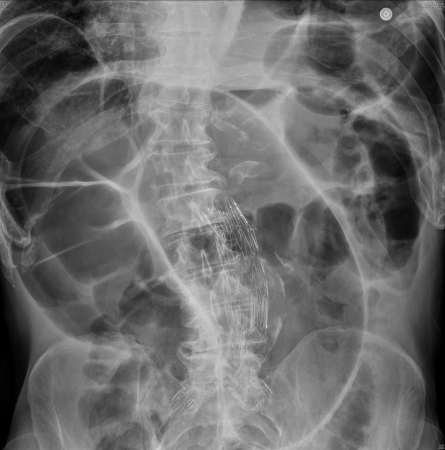

Large bowel obstruction

Abdominal radiograph showing dilated large bowel loops. Typical "coffee bean" sign seen for sigmoid volvulus

Roy SP, Tay YK, Kozman D. Very rare case of synchronous volvulus of the sigmoid colon and caecum causing large-bowel obstruction. BMJ Case Rep. 2019 Jan 28;12(1):bcr-2018-227375; used with permission